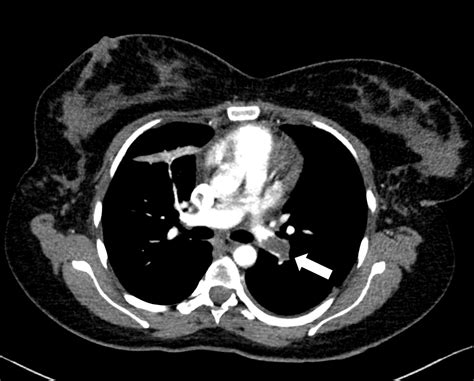

• Suspected pulmonary embolism

However, it’s important to note that the level of radiation exposure varies depending on the type of CT scan and the area of the body being scanned. For example, a CT scan of the head exposes the fetus to less radiation than a CT scan of the abdomen or pelvis.

The radiation dose from a CT scan can vary significantly depending on the type of scan and the area of the body being imaged. The following table provides an approximate range of radiation doses for different types of CT scans:

Type of CT Scan Approximate Radiation Dose (mGy)

Head 1-2

Chest 7-8

Abdomen/Pelvis 10-20

Full Body 30-40

It’s important to note that the risk to the fetus depends not only on the radiation dose but also on the stage of pregnancy. The first trimester is the most critical period, as this is when organogenesis occurs. The risks decrease as the pregnancy progresses.